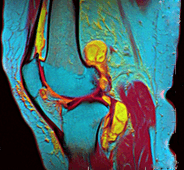

In addition, variants of false color such as pseudocolor (see discussion), density slicing (see discussion), and choropleths (see discussion) are used for information visualization of either data gathered by a single grayscale channel or data not depicting parts of the electromagnetic spectrum (e.g. elevation in relief maps or tissue types in magnetic resonance imaging).

A pseudocolor image (sometimes styled pseudo-color or pseudo color) is derived from a grayscale image by mapping each intensity value to a color according to a table or function.[7] Pseudo color is typically used when a single channel of data is available (e.g. temperature, elevation, soil composition, tissue type, and so on), in contrast to false color which is commonly used to display three channels of data.[4]

Depending on the table or function used and the choice of data sources, pseudocoloring may increase the information contents of the original image, for example adding geographic information, combining information obtained from infrared or ultra-violet light, or other sources like MRI scans.[8]